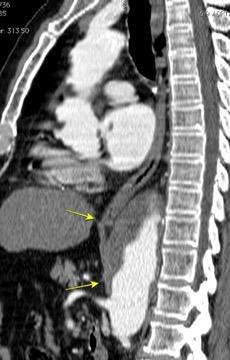

Aneurisma aórtico intracrural

/Restrepo CS et al. The diaphragmatic crura and retrocrural space: normal imaging appearance, variants, and pathologic conditions. Radiographics 2008